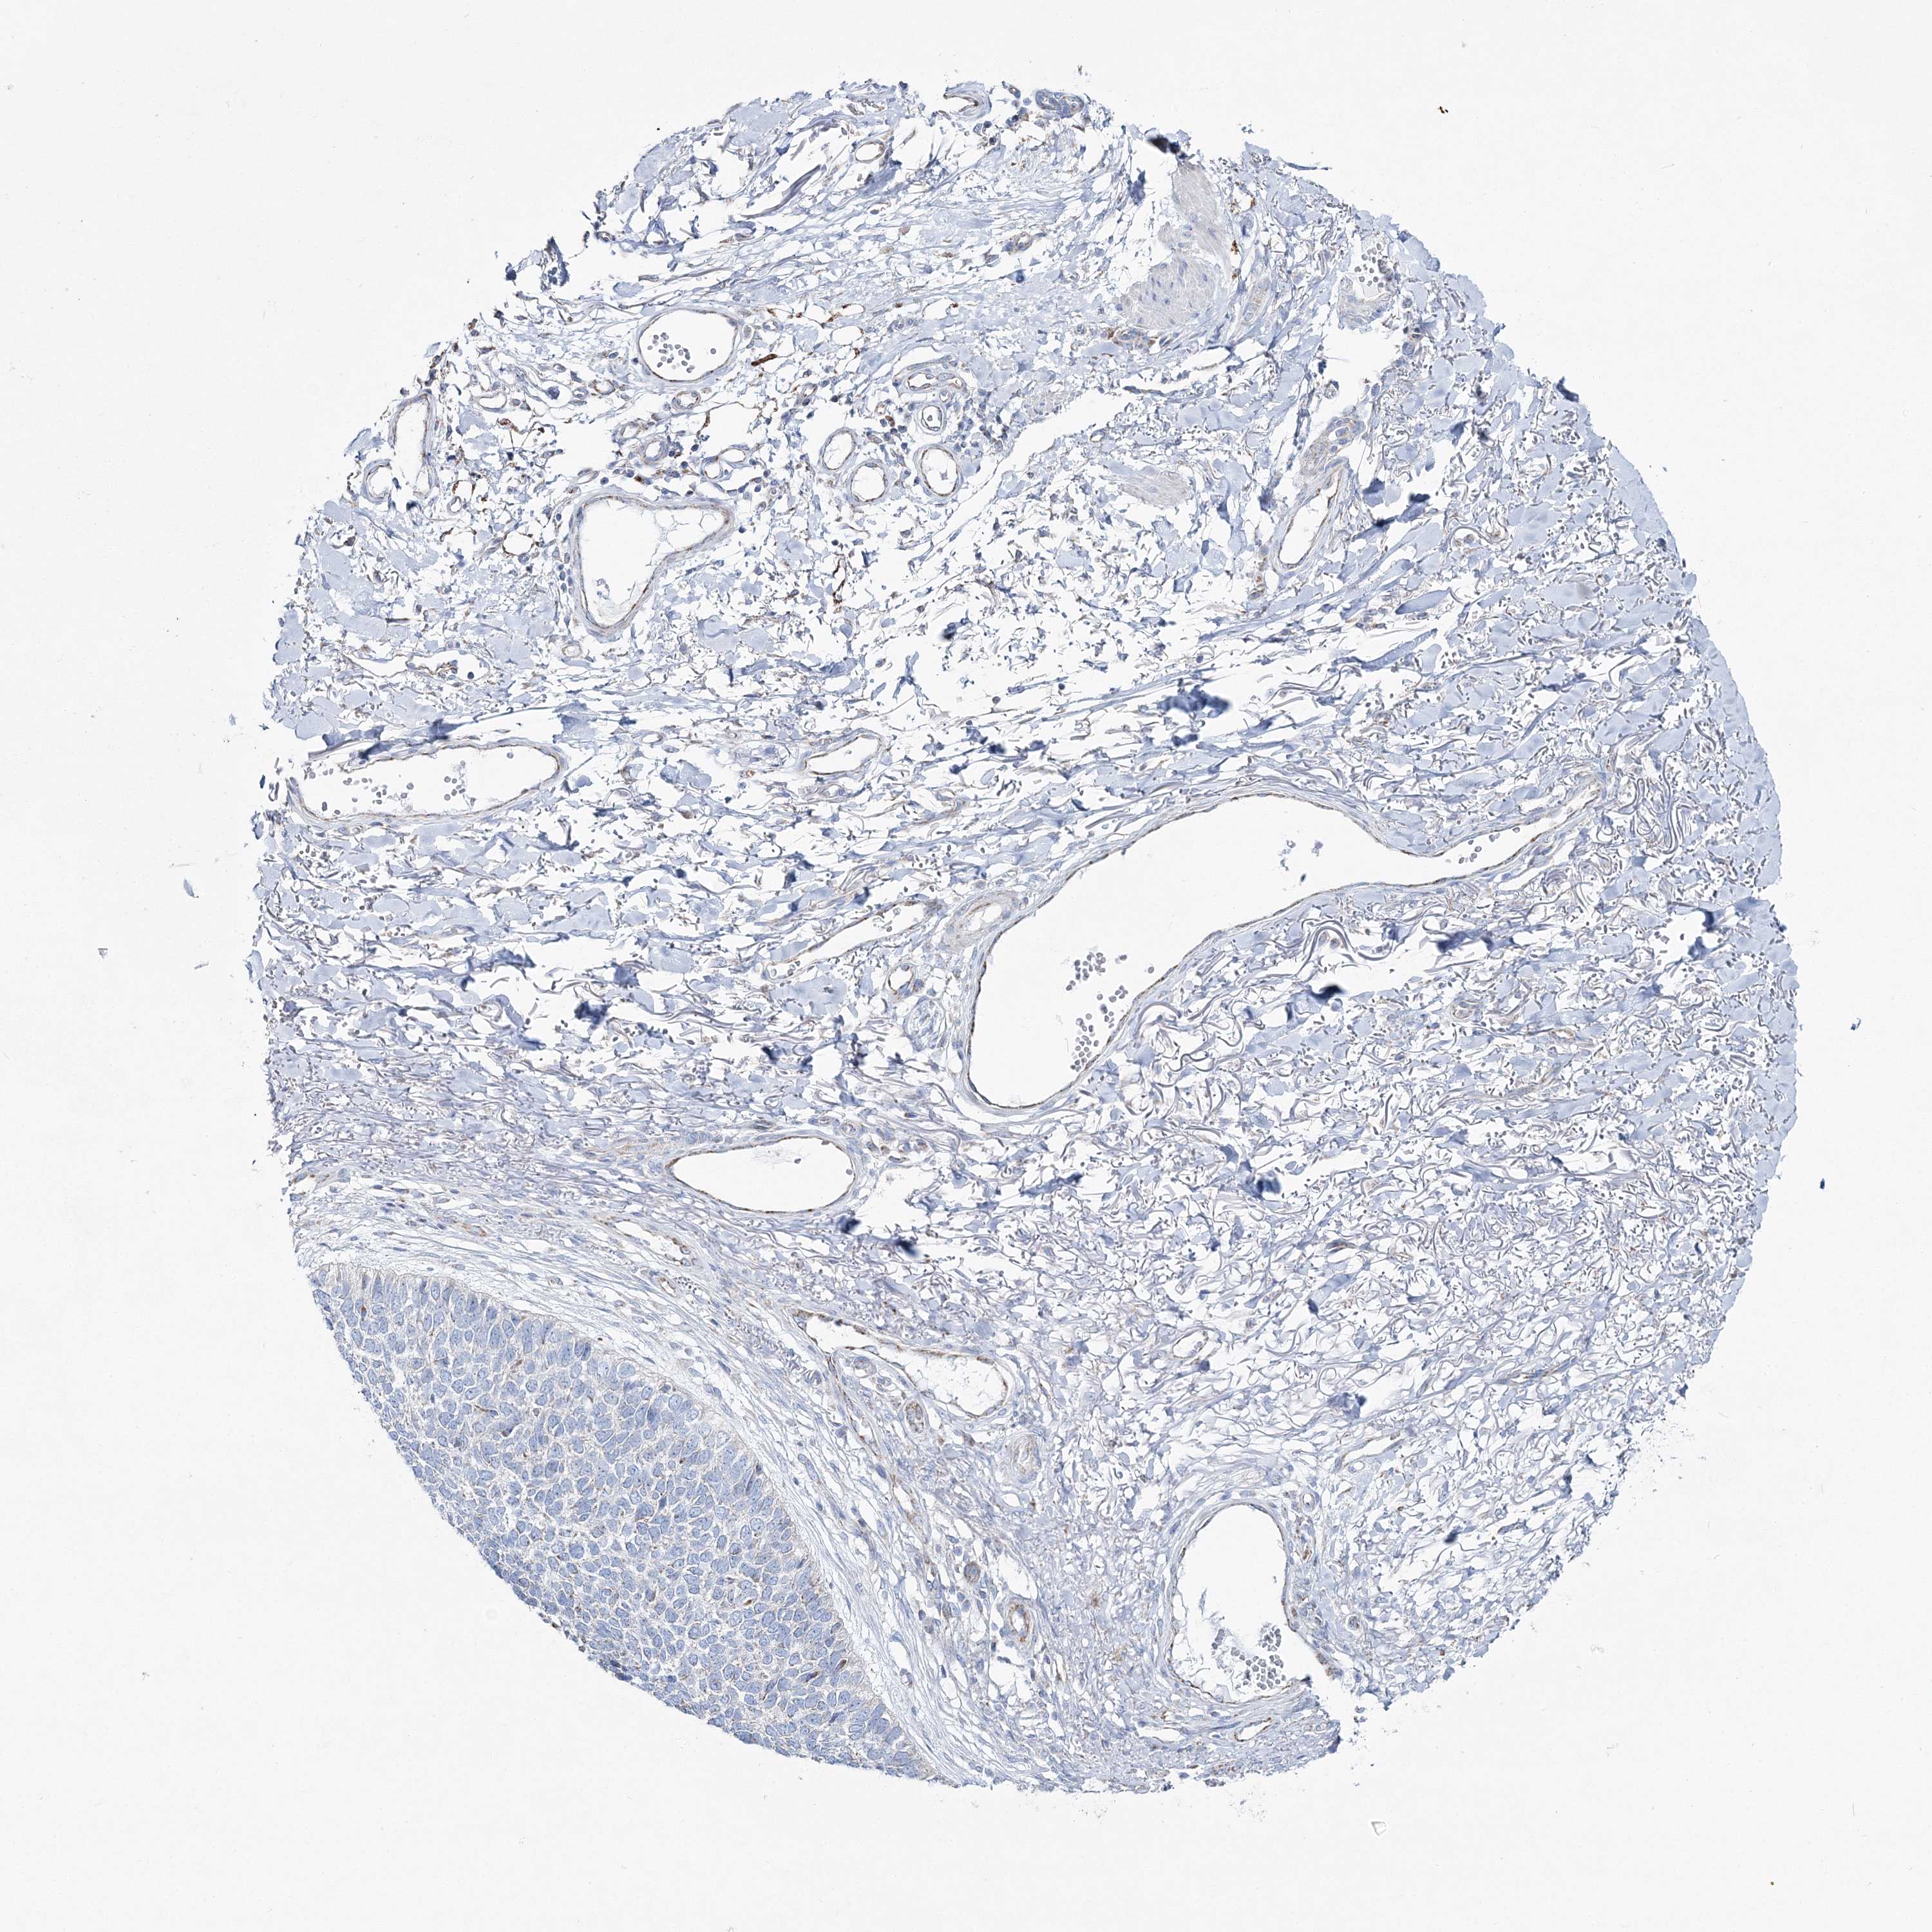

Basal cell and squamous cell cancer

SKIN CANCER - Protein expressioni

A mouse-over function shows sample information and annotation data. Click on an image to view it in a full screen mode. Samples can be filtered based on level of antibody staining by selecting one or several of the following categories: high, medium, low and not detected. The assay and annotation is described here.

Antibody stainingi

Antibody staining in the annotated cell types in the current human tissue is reported as not detected, low, medium, or high, based on conventional immunohistochemistry profiling in selected tissues. This score is based on the combination of the staining intensity and fraction of stained cells.

Each image is clickable and will lead to virtual microscopy that enables deeper exploration of all samples and also displays staining intensity scores, fraction scores and subcellular localization as well as patient and tissue information for each sample.

Antibody HPA036540

Antibody HPA036541

Staining

High

Medium

Low

Not detected

Intensity

Strong

Moderate

Weak

Negative

Quantity

>75%

75%-25%

<25%

None

Location

Nuclear

Cytoplasmic/membranous

Cytoplasmic/membranous,nuclear

Basal cell carcinoma

Squamous cell carcinoma, NOS

Squamous cell carcinoma, metastatic, NOS